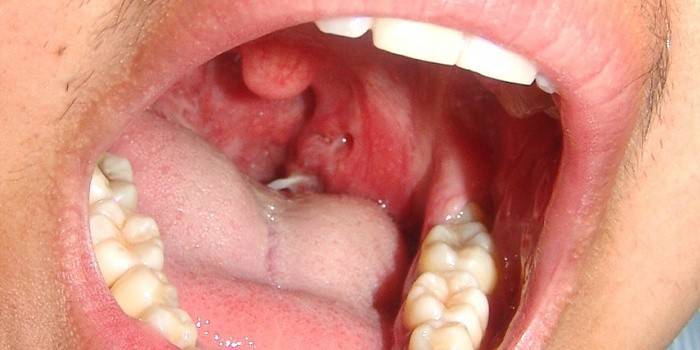

¿Cómo se ve el cáncer de garganta?

Un análisis comparativo de fotografías de cáncer en la etapa inicial y en una fecha posterior le permite ver cambios en la membrana laríngea durante el desarrollo del tumor. En la primera etapa, el tamaño del tumor no supera los 2-3 cm. Aparecen úlceras en la membrana mucosa de la laringe, que también son visibles en la foto. Esto se puede ver durante el examen realizado por el dentista y recomendar más investigación. En las imágenes, el área afectada de la laringe es muy diferente de los tejidos sanos.